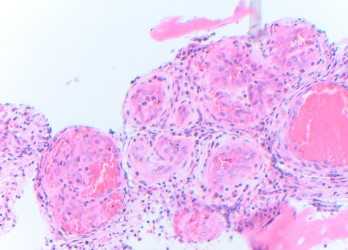

Microscopic sections show a proliferation of well-formed small blood vessels with lobular arrangement and occasionally arranged around small arteries. The small vessels are formed by epithelioid endothelial cells that display abundant eosinophilic cytoplasm and enlarged round nuclei, and normal to low nuclear-to-cytoplasmic ratio; while in more cellular areas the nuclei become elongated. The stroma is hemorrhagic to edematous with mixed inflammatory cells including numerous eosinophils, which may be a clue to the diagnosis in small biopsies.

The tumor cells express endothelial markers such as CD31, CD34, FLI1, ERG and factor VIII-related antigen. In this case, immunohistochemistry was used to demonstrate that the epithelioid endothelial cells were positive for the vascular marker ERG. Most cases show rearrangement of FOS or FOSB. The histopathologic differential diagnosis should include angiosarcoma, which is not typically well demarcated, lacks the lobular architecture, shows more cytologic atypia, and has significant proliferative activity (absent in this case). Metastatic carcinoma is negative for vascular markers. Epithelioid hemangioendothelioma shows hyalinized or chondroid stroma and vacuolated cells